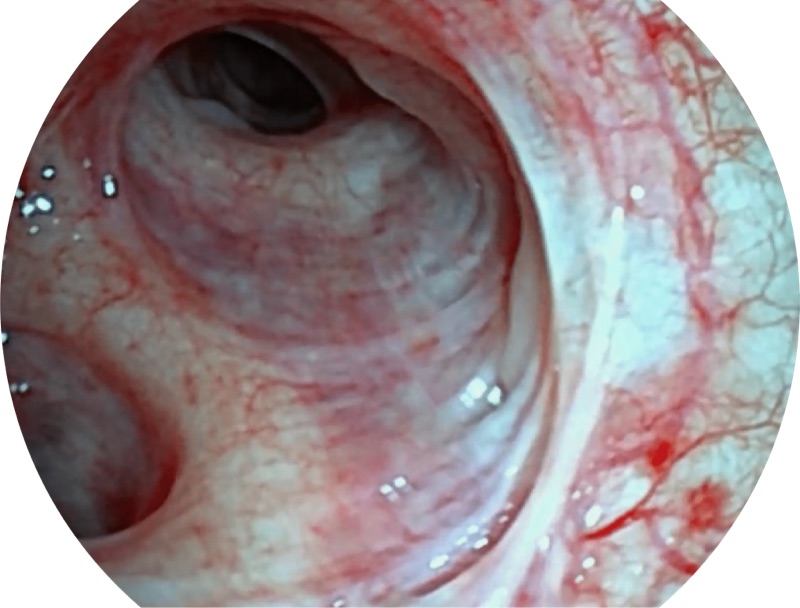

VIST

帮助医生更加清晰地观察气管表面病灶